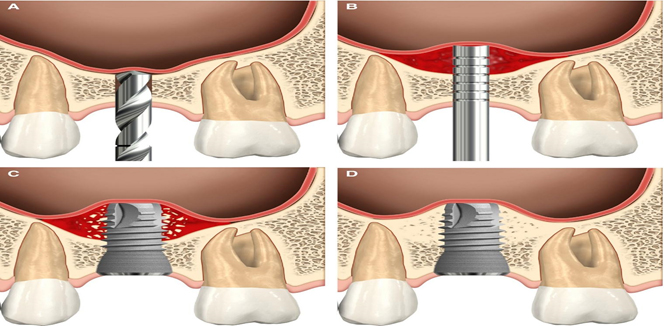

What is Sinus Lift Surgery for Dental Implants? Do I Need One? Sinus lift surgery which is also called sinus…